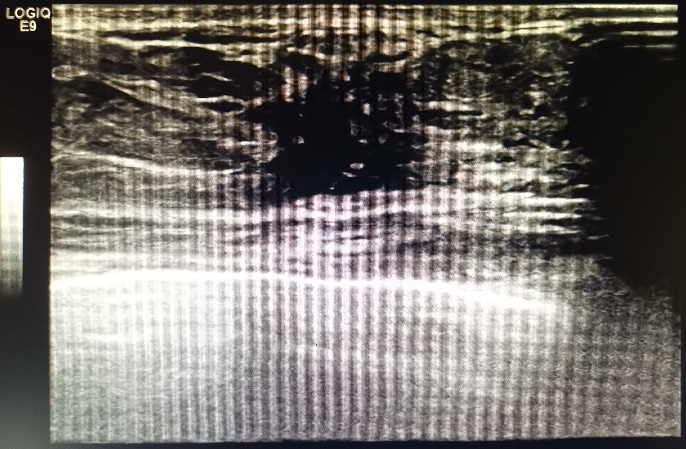

彩超:左乳中央腺体层可见大小约4.10×1.80cm的低回声团块,边界不清,边缘毛糙,其内回声分布不均匀,CDFI示血流信号Ⅲ级。双侧腋窝及双侧锁骨上下未见明显肿大的淋巴结。

彩超提示:1. 左乳外上及内上低回声团块,BI-RADS-US 4a类;